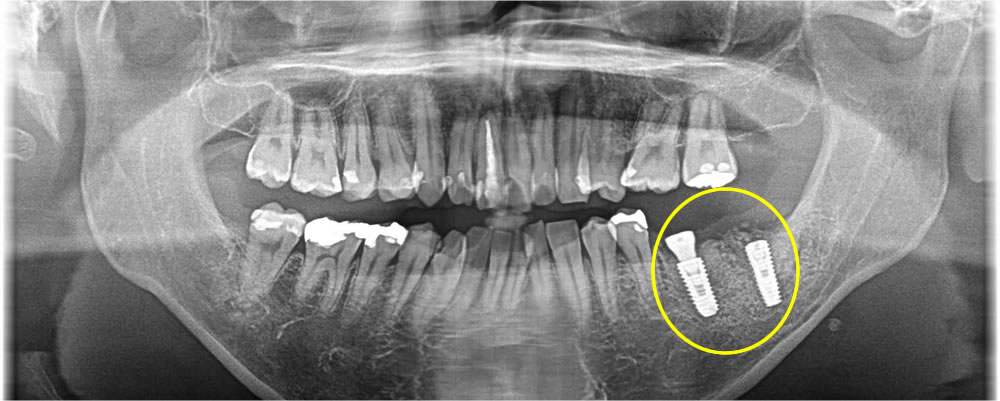

CT検査にて根の先に大きく膿が溜まり、骨が溶けてしまっている事が確認されました。1番奥の歯と2番目の歯にも確認されましたが、患者さまのご希望により、1番奥の歯のみを抜歯し、インプラント治療を行う事になりました。

まず歯を抜き、中の膿を綺麗に取り除いた後に即時でインプラントを埋入し、骨の無くなってしまっている場所に骨造成を行いました。こちらは減張切開を行い、創の完全閉鎖をしました。

固定もしっかりと得る事ができ、4ヶ月置いて進めていく予定でしたが、途中で1つ前の歯も痛みだしたため、やはりこちらの歯も抜いてインプラント治療を行いたいという事になりました。

1つ前の歯も抜歯後に中を綺麗にし、インプラント埋入、骨造成までを1度のオペで行っていきました。こちらはインプラントの蓋が外に出るような形にして縫合しました。